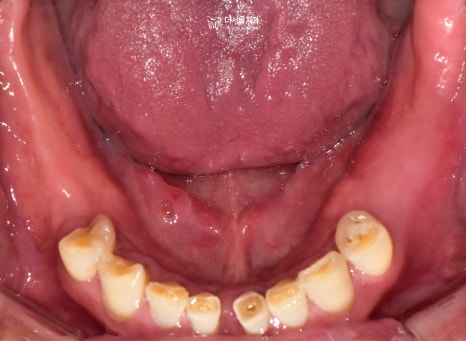

초진 구강 사진을 보면

곳곳에 이가 빠져서 빈 곳이 있고

남아있는 이들이 깨지고

벌어져있습니다.

바로 어금니가 없기 때문입니다.

식사를 할 때 중축이 되는 대구치는

총 8개가 있어야 되는데요.

현재 3개밖에 남지 않았으며

맞물리는 이가 없어서

제 기능을 하지 못하고 있죠.